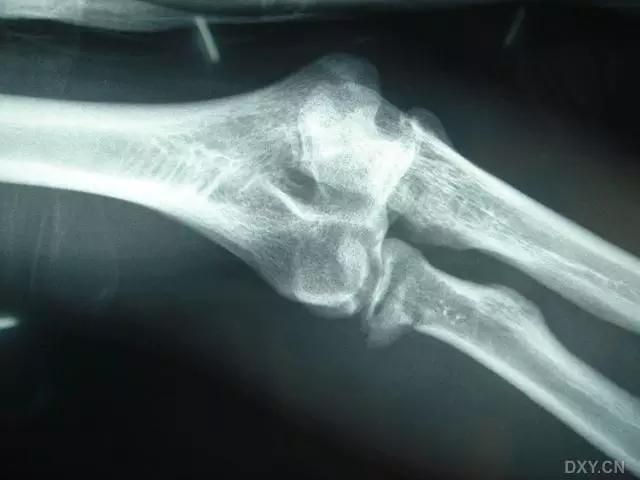

6. Hahn-steinthal 骨折

全肱骨小头骨折,为一种少见的关节内骨折,多见于成年人。常由于跌倒时手过度伸直或在屈肘时因桡骨小头撞击肱骨小头,并同时有外翻力存在时发病,亦可伴有滑车骨折与内侧副韧带的撕裂。X 线表现为全肱骨头骨折,向上移位。

Hahn-steinthal 骨折 X 片(来源:Hahn-Steinthal fracture: a case report.BioMed central Cases Journal20081:239)

Hahn-steinthal 骨折 CT 片(来源:Hahn-Steinthal fracture: a case report.BioMed central Cases Journal20081:239)